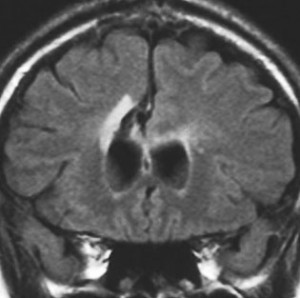

80代の女性に偶然見つかったものです。右の島のグリオーマ insular gliomaで,ガドリニウム増強されないびまん性グリオーマです。右側は2ヶ月半後のMRIで,とても早く広がっていますので,生検術をしました。組織診断は,壊死や微小血管増生はなく,びまん性星細胞腫グレード2でした。TERT promotor mutant, IDH1 WT, IDH2 WT, H3F3A-K27 WT, H3F3A-G34 WT, m HIST1H3B WT, 1p/19q intact, CDKN2A/2B negativeです。

この例は,molecular GBMつまり,glioblastoma IDH-WT WHO grade 4と診断されます。